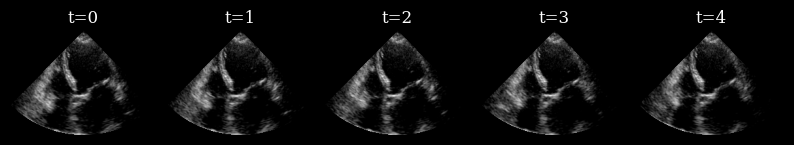

Initially, we have not yet acquired any measurements, so we draw samples from the prior to drive our actions.

[9]:

prior_samples = model.sample(n_samples=n_prior_samples, n_steps=n_unconditional_steps, verbose=True)

scan_converted_prior_samples = scan_convert(

data=keras.ops.squeeze(prior_samples, axis=-1), **parameters

)["data"]

posterior_variance = ops.nan_to_num(ops.var(scan_converted_prior_samples, axis=0))

fig, _ = plot_image_grid(

list(scan_converted_prior_samples) + [translate(posterior_variance, range_to=(-1, 1))],

titles=[f"Sample {i}" for i in range(n_prior_samples)] + ["Var[x]"],

vmin=-1,

vmax=1,

cmap=["gray"] * n_prior_samples + ["inferno"],

)

90/90 ━━━━━━━━━━━━━━━━━━━━ 12s 46ms/step

../../_images/notebooks_agent_agent_example_17_1.png

Next, we implement a perception-action loop, using a greedy entropy minimization strategy to select which lines to acquire next in the sequence. Each set of generated posterior samples at time \(t\) are used as initial samples for the reverse diffusion at time \(t+1\) [1], ensuring that we generate a reconstructed sequence that is coherent over time.